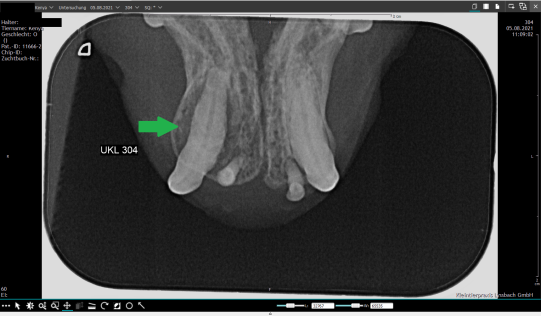

Im linken Unterkiefer lassen sich beispielsweise zwei verschiedene Krankheitsprozesse erkennen: Der Eckzahn (Zahn 304) weist eine Entzündung des Zahnfachs auf: Der Knochen um die Wurzel des Zahnes ist durch die chronische Entzündung stark aufgetrieben und der Zahn wackelt entsprechend (grüner Pfeil). Die hintere Wurzel des letzten Kauzahns (Zahn 309) ist zerfressen, hier handelt es sich um eine sogenannte FORL-Schädigung (roter Pfeil). Die beiden restlichen Zähne weisen Komponenten beider Erkrankungen auf.

UKL